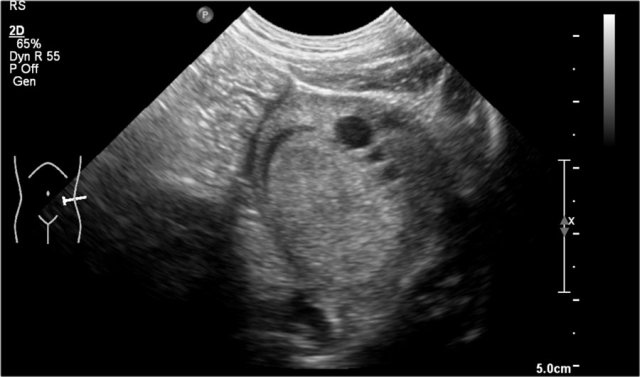

One-year-old boy was referred with a diagnosis of a cystic nephroblastoma.

Ultrasound detected a huge cyst in the middle of the abdomen.

When examined from the left flank with a high frequency linear array probe some parenchymal tissue was visible surrounding very dilated calyces. This is compatible with an extreme hydronephrosis.

At first it was thought that there were some solid parts in the cyst.

But when pressure was applied with the probe this proved to be debris.

MRI depicts the hydronephrosis with more overview.

The cause was a pyeloureteric stenosis.

The left kidney had 33% split renal function on renography.

A pyelum reconstruction was successfully performed.